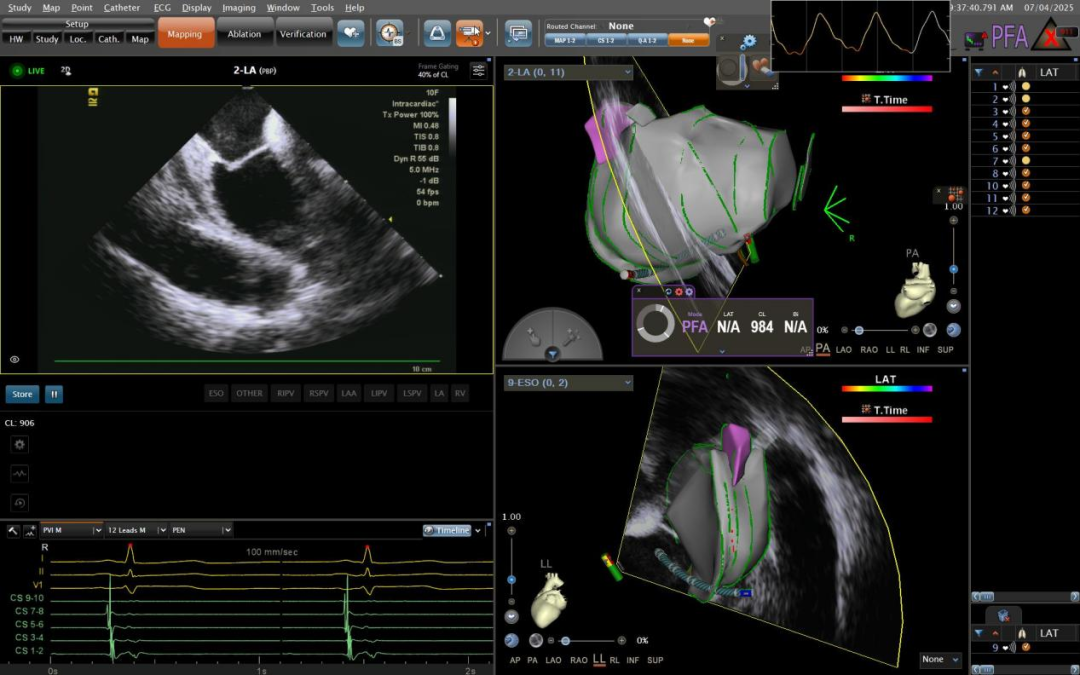

近日,江苏省人民医院重庆医院在杨刚院长、王骋及叶昌伦主任带领下,成功完成零射线(ICE)指导下VARIPULSE脉冲消融房颤手术。该技术通过三维电生理标测系统(CARTO 3)与脉冲电场消融(PFA)的深度整合,实现了房颤治疗的精准定位与安全消融,标志着我国房颤治疗正式迈入“三维可视化脉冲消融”时代。

术中数据显示,单台手术平均时间缩短至120分钟以内,肺静脉隔离时间仅需5分钟/支,术中全程射线量0,相较于传统消融方式实现了绿色手术造福患者,且术后恢复时间大幅缩短。,且患者术后恢复时间大幅缩短。

三维解剖重建,手术路径实时追踪

VARIPULSE可与CARTO系统无缝集成,全程三维可视,能够还原左房解剖,追踪消融损伤路径,帮助术者以更安心、高效的方式开展手术。它不仅能与心腔内超声(ICE)产品进行整合,提供实时成像,保障低/零射线手术的顺利开展,还可通过局部阻抗TPI显示电极与组织的贴靠程度,来确保有效放电。

脉冲消融优势:高效性与安全性并重

临床数据显示,VARIPULSE在欧洲inspIRE试验中,通过对186名患者的临床研究,实现随访12个月0%主要不良事件(包括肺静脉狭窄、心房食管瘘、血栓栓塞、短暂性脑缺血发作、卒中或心肌梗死等),接受优化PFA治疗方案的患者12个月的临床成功率近80%,且整合CARTO 3的PFA平台X线透视时间显著缩短,手术时间也更短。